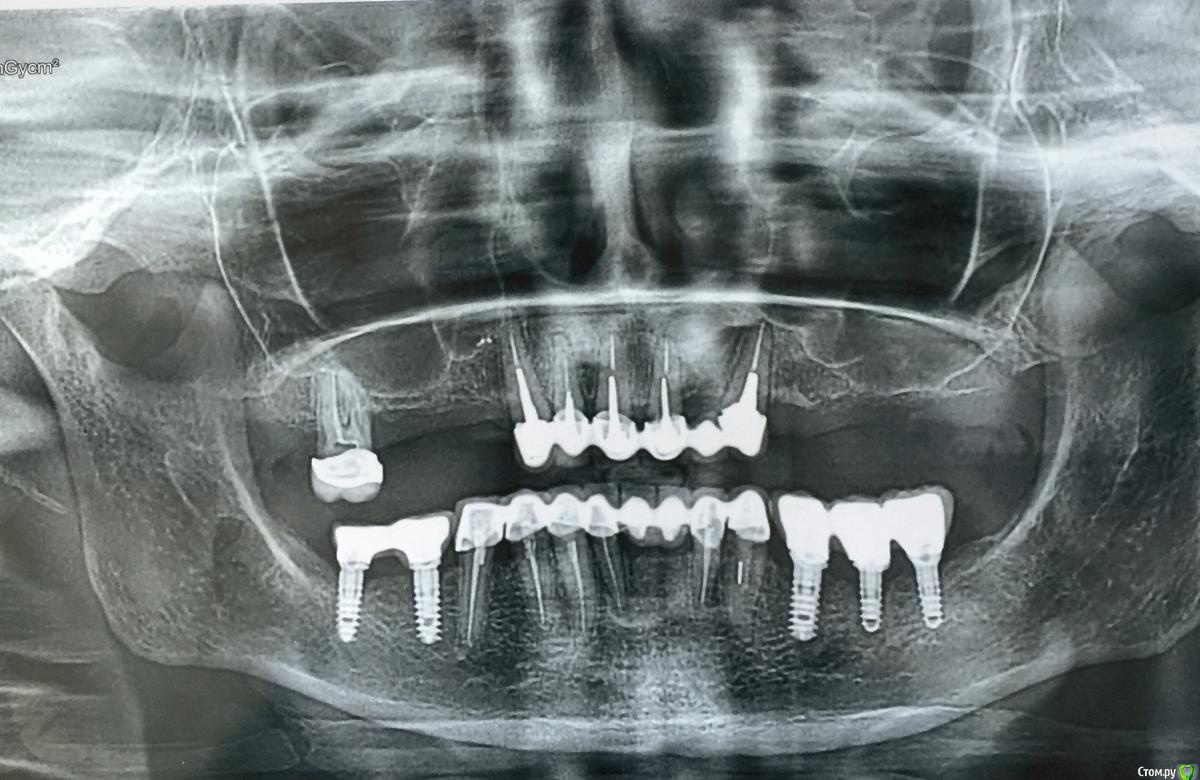

Уважаемые доктора, после установки 34,36,37 имплантатов появилась пульсирующая боль, по результата оптг, (ушла кость)было принято решения удалить 36 имплант,имплант был хорошо интегрирован , воспалительного процесса небыло,после удаления

пульсация сохранилась, может ли быть причиной 33 зуб, где сломан файл,есть ли там кариес?